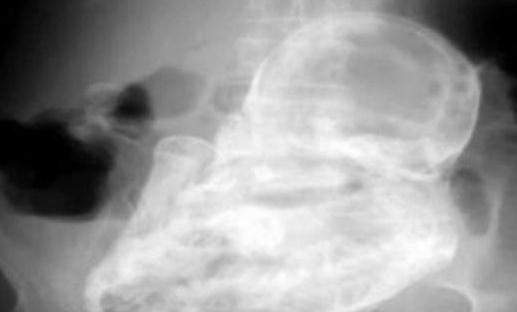

这个孕妇是位82岁的老太太,她因剧烈的腹泻而到该医院就诊。在全面的临床检查之后,医生确定她的腹部并没有结石或肿瘤。

(本文来源于图老师网站,更多请访问http://www.tulaoshi.com)不过,接下来的发现却让所有人吓了一大跳——老太太的子宫外竟然有个未发育的胎儿,但已经死亡了近40年。

这个“石化胚胎”是怎么形成的呢?医生解释称:“由于胚胎未在子宫里发育,移动到老妇的腹腔,导致胚胎无法正常生长,因而钙化形成石胎。”